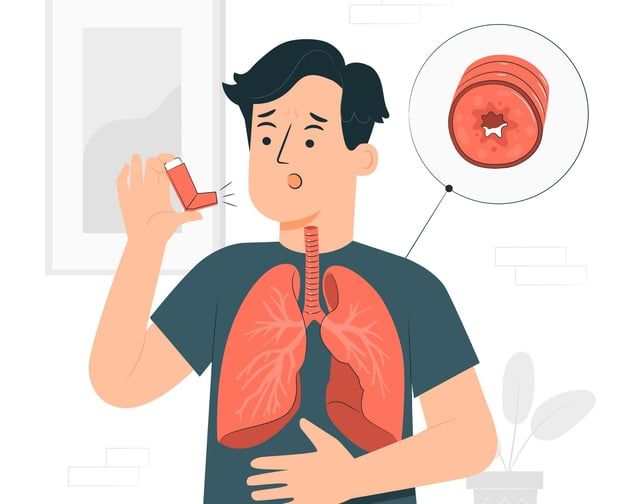

Lung-Related Causes

Pneumonia

Pleurisy

Pulmonary embolism

Pneumothorax (collapsed lung)

These often present with sharp or stabbing pain and need urgent medical care.

When chest pain is linked to gastrointestinal problems, it can often be managed through lifestyle changes, acid-reducing medications, or antibiotics for infections. For lung-related issues like pneumonia, pleurisy, or a collapsed lung, treatment may include antibiotics, pain relievers, or medical procedures to remove fluid or reinflate the lung.